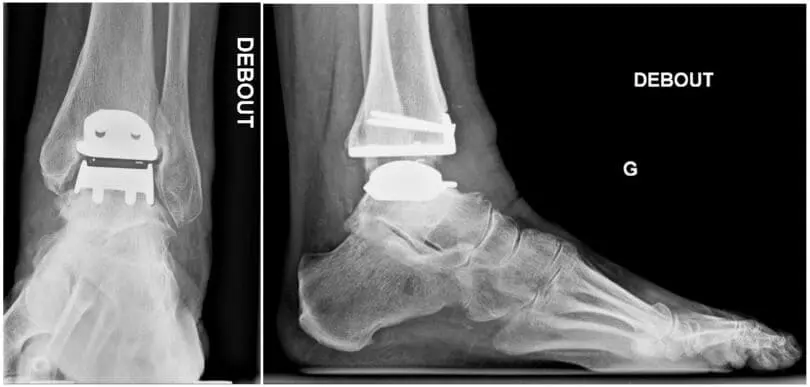

Prosthesis: With this, the diseased joint is replaced with an artificial joint. If adjacent joints, whether or not symptomatic, show signs of osteoarthritis, and in case you persist in maintaining the joint mobility, we can implant a prosthesis.

Recently, there is a reimbursement for the various components of the prosthesis, but only in certain cases. In addition, there has to be a correct follow-up in the years after the operation.The advantages are the preservation of motion, through which one protects the adjacent joints, and the fact that patients – if wearing a walker – are allowed to lean after 3 weeks already. However, the major disadvantage is that a prosthesis of the ankle has a shorter life span than at the knee or hip. Often, one has to perform a revision with prosthesis or arthrodesis after 10-15 years.